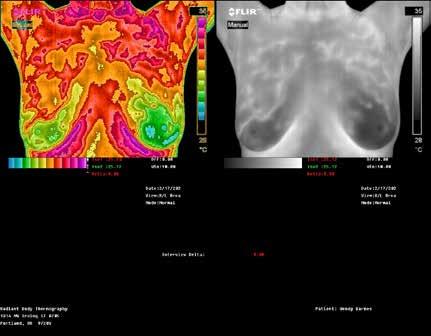

RADIANT BODY

THERMOGRAPHY

The Canary in the Coal Mine

RADIANT BODY THERMOGRAPHY

Candace Parmer

Clinical Thermographic Technician 503-775-1812

RadiantBodyThermography.com

CBD Oil

Call to learn how we can assist you and your doctor in protecting breasts from disease, excess hormonal activity and over diagnos breast cancer. See ad, page 17.